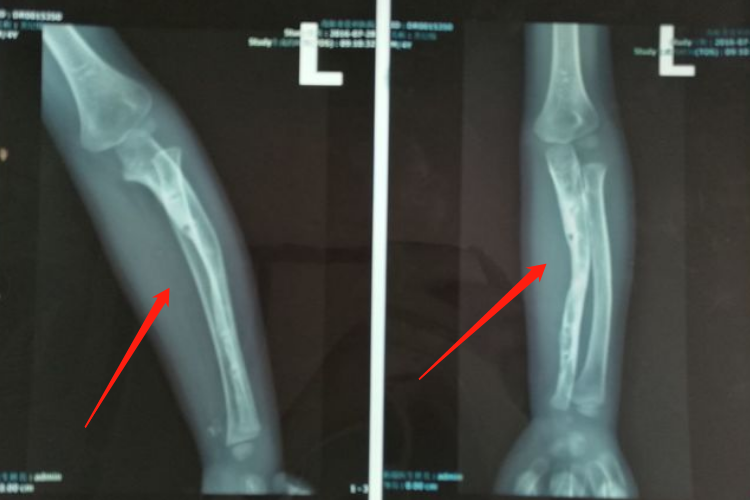

骨痂是骨延长愈合过程中新形成的连接骨折两端的骨组织,骨延长骨痂生长过程中先形成纤维骨痂再形成骨性骨痂。

在骨延长术后两周左右,由于早期大量的纤维细胞、成骨细胞等增殖活动,分泌出大量基质、成纤维细胞和成骨细胞,形成纤维骨痂,可包围并固定骨两端。

纤维骨痂形成后,成骨细胞活跃,分泌出均质透明的类骨基质,继之形成类骨组织,而后钙质在类骨基质间不断沉积形成骨组织,此时骨痂称为骨性骨痂。